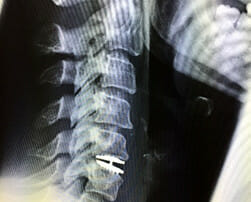

Bandscheibenprothese bei Bandscheibenverschleiß und Bandscheibenvorfall der HWS anhand eines Fallbeispiels im OZA München Wirbelsäulenzentrum, Prof. Dr. med. Oliver Linhardt

Abbildung 1 zeigt das seitliche MRT Bild einer 38-jährigen Patientin mit Schmerzen der Halswirbelsäule und auch der Arme seit 8 Monaten. Konservative Maßnahmen mit Physiotherapie, Osteopathie und gezielten Injektionen [...]